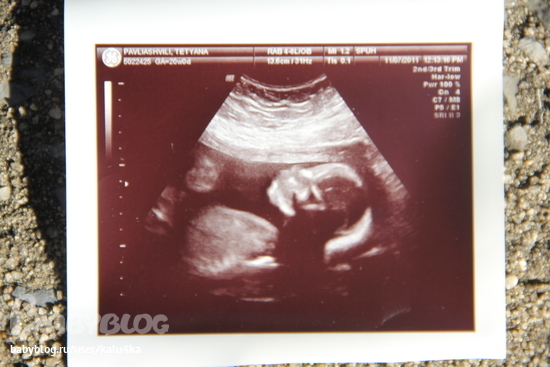

О хорошемИтак ходили сегодня на узи с мужем и доченькой)) .главное конечно то, что все у нас хорошо, дете здоровое и крепкое, вес приблизительно 400 грамм, сердечко в норме, внутренности в норме, пальчики-ручки-ножки все в норме)Устраивал там нам показательное выступление, не секунды покоя, ноги выше головы, пальцы сосем, язык показываем. кароче насмеялись там с мужем и врачихой)

Вобщем когда мне показали фото, того самого причинного места, я и ахнула)) врачиха поняла все и говорит - да.да папочка, я на Вашем месте бы гордилась сыном))) муж покраснел, но сидит такой гордый, грудь вперед)) Вобщем и наконец-то фото нашего сыночки)

на то самое место указывают стрелочки))